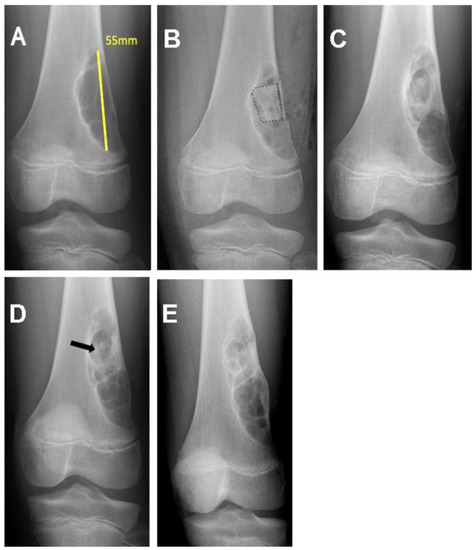

| 17/M/11 | Distal femur | Nonossifying fibroma | 7.11 |